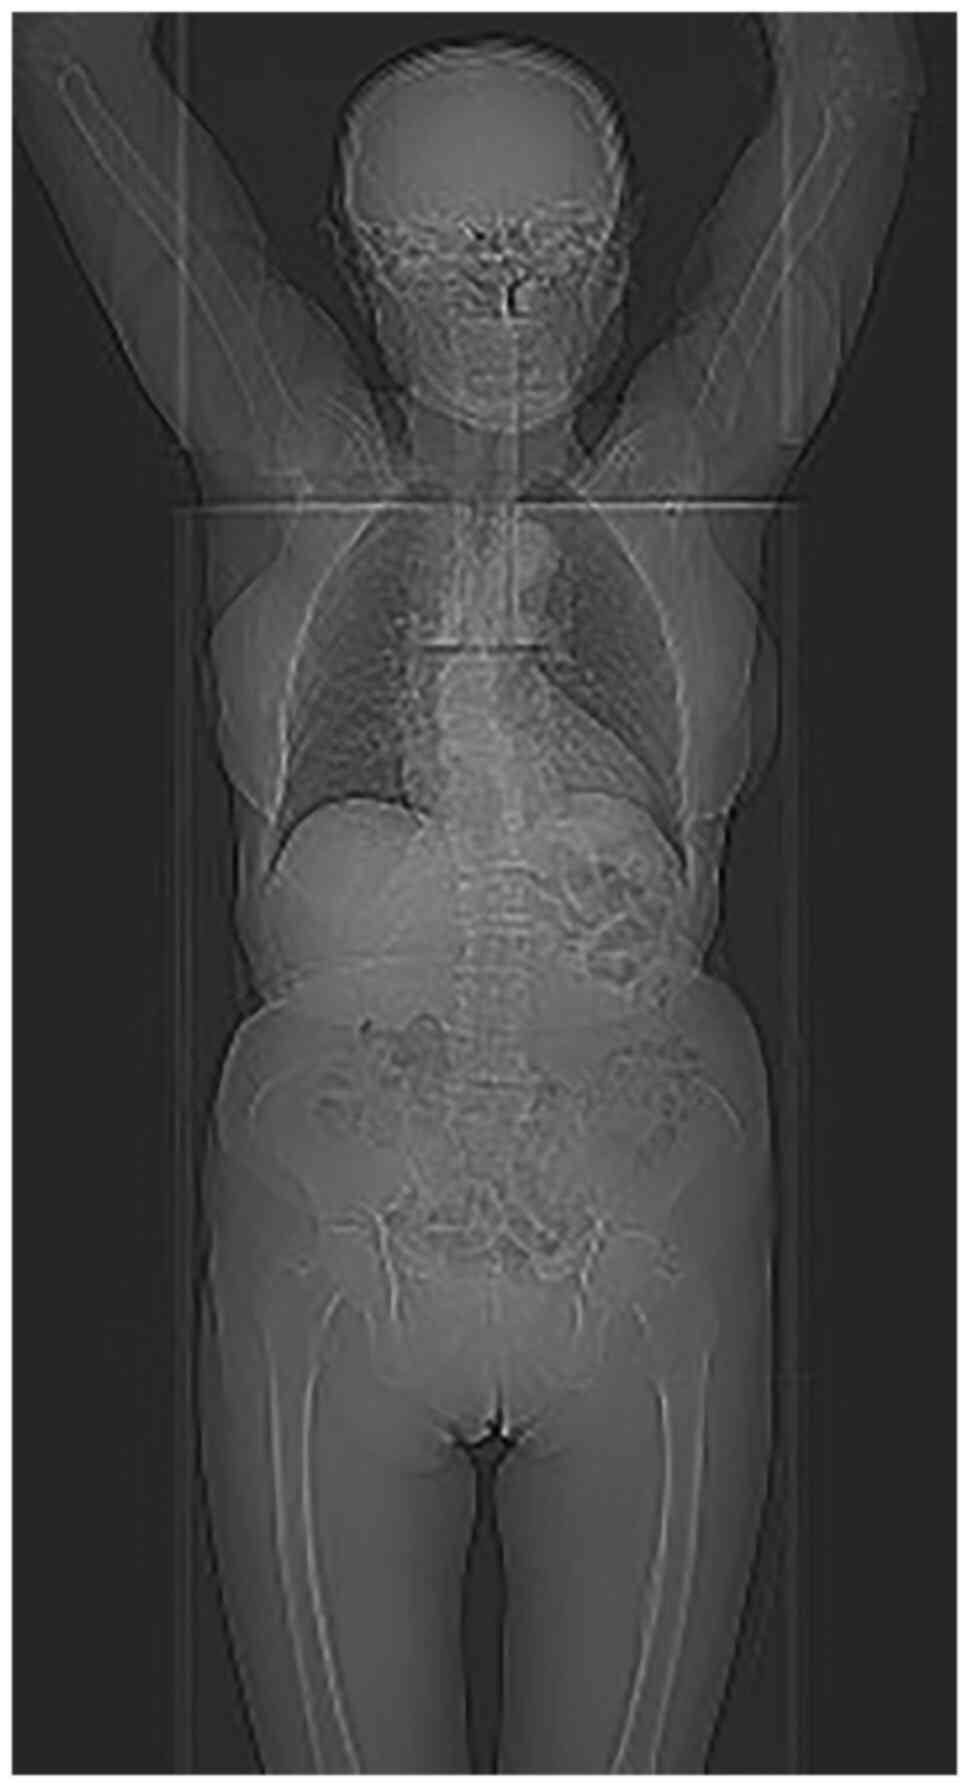

An unusual non‑metastatic, mismatch repair‑deficient primary gastric squamous cell carcinoma presenting as a large, exophytic, bleeding tumor: A case report

Primary gastric squamous cell carcinoma (GSCC) is an extremely rare malignancy with a poor prognosis. Despite the improved knowledge regarding its pathogenesis and biology, the treatment options remain limited. The present study reported on the unique case of a mismatch repair‑deficient (dMMR) primary GSCC in a 79‑year‑old woman reporting fatigue and symptoms of upper gastrointestinal tract bleeding. Physical examination revealed abdominal pain at palpation. Gastroscopy revealed a large, exophytic, bleeding tumor. Medical imaging confirmed a mushroom‑like polyp in the lumen of the stomach, with no signs of disease spread. Total gastrectomy and D2 lymphadenectomy were performed. Pathological examination of the post‑operational material confirmed a well‑differentiated SCC invading the mucosa, submucosa and muscle layer. There were no signs of dissemination observed in any of the 32 excised lymph nodes. Notably, according to the last follow‑up, the patient remains well, supporting the 5‑year GSCC survival rate statistics. To the best of our knowledge, this is the first such GSCC case reported in the Surgical Oncology Outpatient Clinic (Copernicus Memorial Hospital, Lodz, Poland) and these findings add to the limited data on GSCC. Although this is a very rare condition, it should always be considered during the process of diagnosis of gastric tumors.